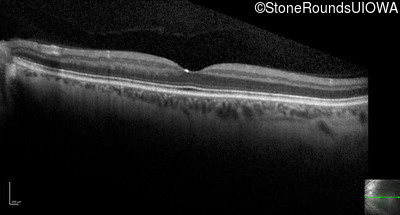

Optical Coherence Tomography - Right - 20/200

Exemplar / OCT Stack

OCT Stack